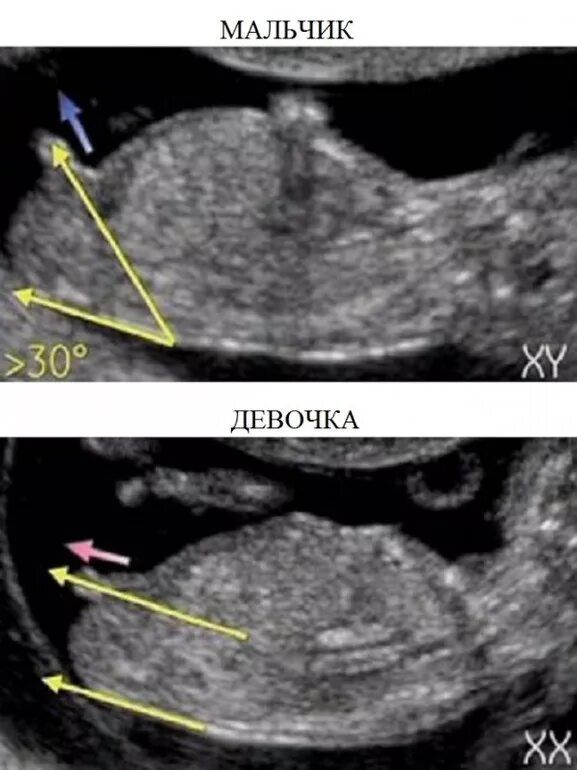

На узи можно определить раннюю беременность